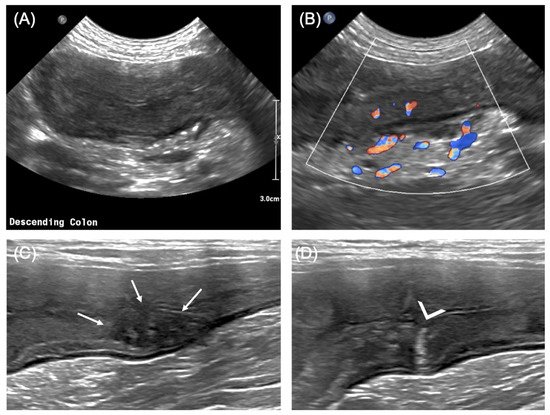

2.2. Imaging Diagnosis